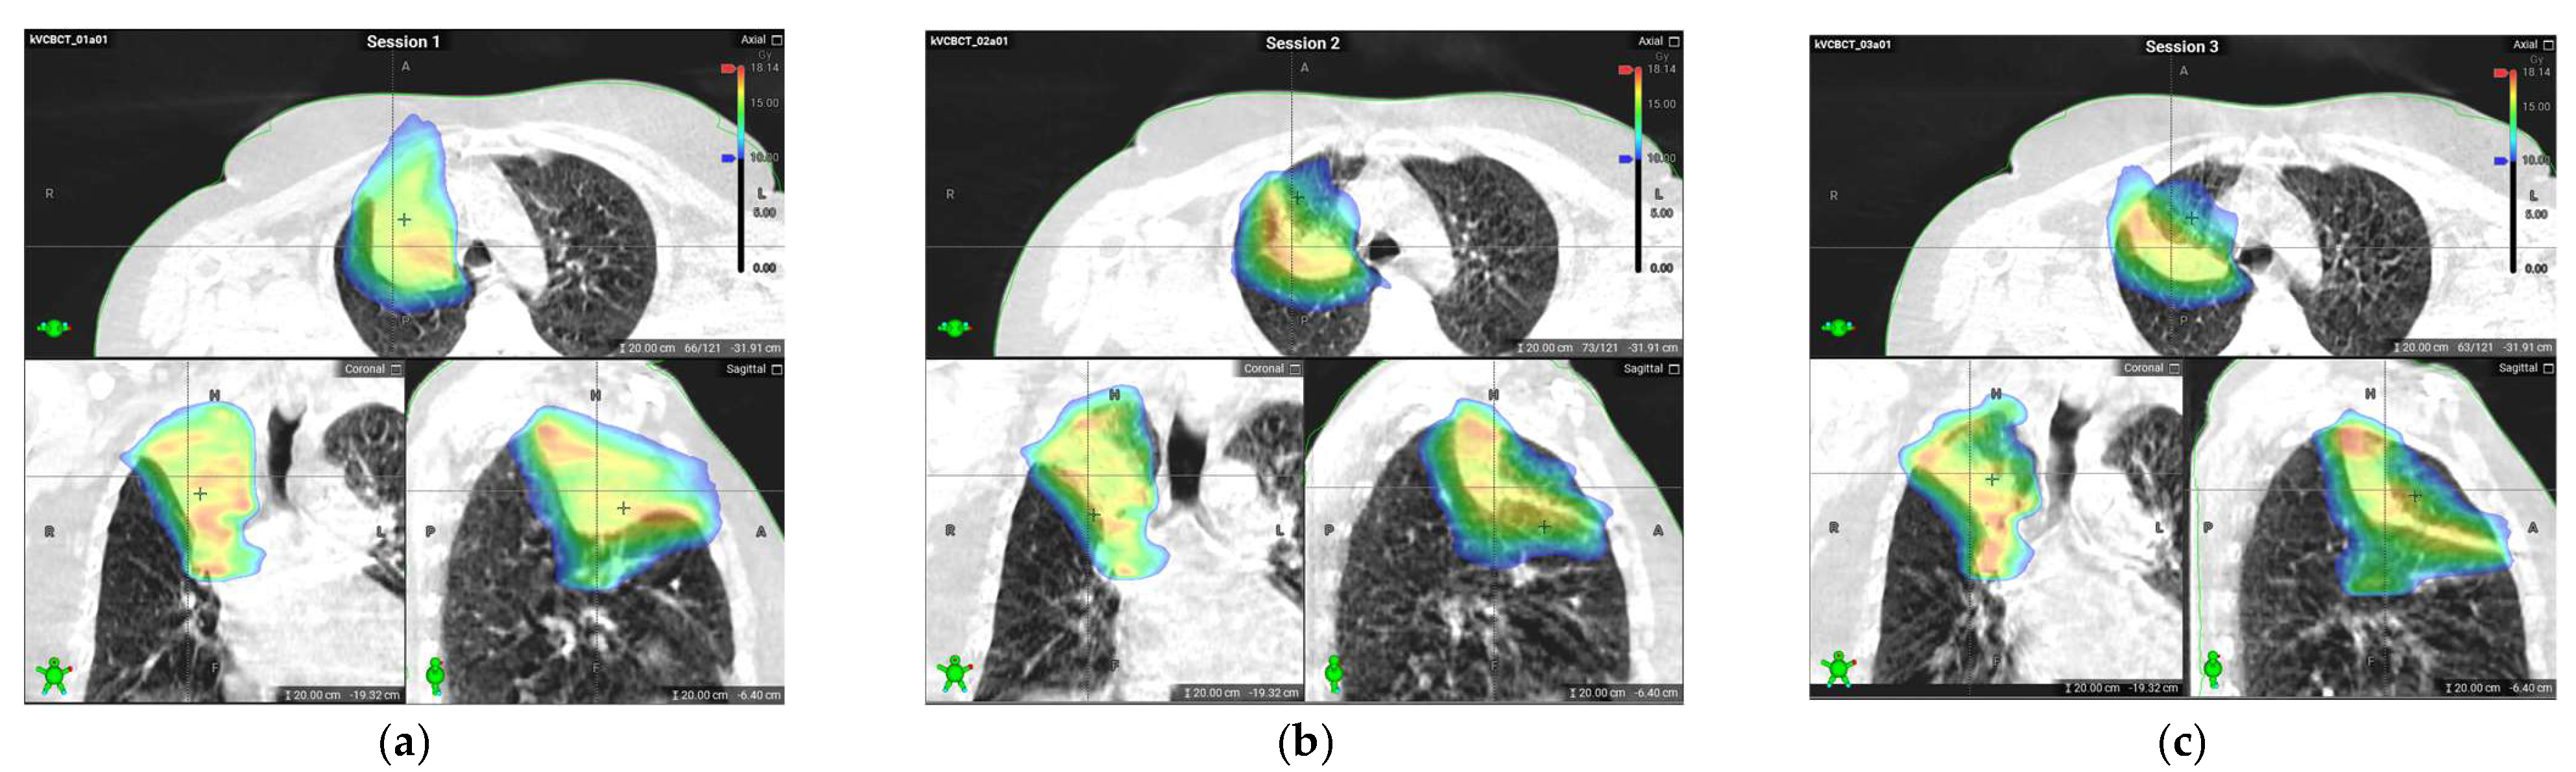

A substantial reduction in tumor volume resulted in a smaller ITV and a reduced dose to the surrounding organs, as seen in Figure 1.

In-house three-fraction volume dose constraints to the ribs (volume receiving 28.8 Gy should not exceed 1 cm3), tracheobronchial tree (volume receiving 15 Gy should not exceed 4 cm3), and lung (volume receiving 20 Gy should not exceed 10% and must be less than 20 of the lung) were used in plan optimization and evaluation. Since the total dose was delivered in three pulses, volumes of OARs receiving one-third of the constraint dose are reported and compared between pulses, as shown in Table 1.

Maximum doses (listed as doses delivered to 0.1% of the volume of the OAR) are also compared between pulses for the tracheobronchial tree, aorta, and pulmonary artery, as shown in Table 2.

The reduction in target volume after the pulses (followed by pauses) resulted in a significant decrease in the dose to healthy tissue for all tissues except for the lungs. Due to tumor shrinkage, more lung tissue in the apical segment was exposed to a high dose when comparing the second and third pulse with the first one.

In our case, the initial and second pulses resulted in a significant ITV reduction of 18% and 28%, leading to better overall OAR sparing during the second pulse, as observed by Moore et al. [6], Sezen et al. [7], and Rahimian et al. [9].

Figure 1. Comparison of dose distributions delivered during the first, second, and third pulses: (a) dose distribution delivered based on cone beam computed tomography (CBCT) images acquired during the first pulse; (b) dose distribution delivered based on the CBCT image acquired during the second pulse, four weeks after first pulse; (c) dose distribution delivered based on the CBCT image acquired during the third pulse, eight weeks after the first pulse. A substantial reduction in lesion size and dose to the surrounding tissue can be seen.